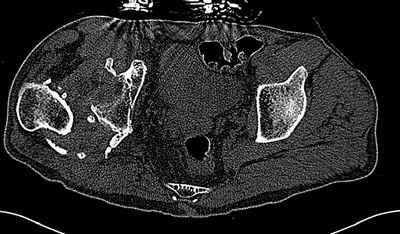

Уважаемые коллеги. Пациент 30 лет 3 года назад в результате травмы получил травматический дефект нижних конечностей до в/3 голеней, был пропущен вывих бедра.

В настоящее время очень неплохо ходит на протезах, движения в неоартрозе близки по объему к здоровой стороне. Основная жалоба - выраженная боль при ходьбе. планируем двухэтапное эндопротезирование - задним доступом мобилизовать проксимальный отдел бедра, резецировать шейку, аппаратом низвести бедро(головку оставить там где она есть, так как больших дефектов не видно(может пригодится в последующем?)). Вторым этапом бесцементное эндопротезирование. Насколько такой вариант реалистичен? Доступ для второго этапа? Может быть другие варианты?С уважением, Максим

На последнем срезе КТ задний край практически отсутсвует по сравнения со здоровой стороной. Разумеется, что это плоскостное изображение, но головка вывихнулась не только в плоскостную щель захваченную на КТ. Если вы считаете, что удастся установить туда чашку даже низкопрофильную, остается пожелать вам успехов. Но перед этим можно смоделировать установку чашки на скиаграммах КТ.

За пожелание успехов - спасибо, думаю это пригодится, не очень понял про плоскостную щель, специально предоставил срезы на уровне свода - он цел, дефект заднего края ниже, за счет заглубления он будет еще меньше, по данным 3d - должно получиться.

Решение по ВВ придется принимать по месту.... Сумеете "подрыться" и получить хорошее покрытие чашки (+2 винта об-но) - хорошо, если нет -

костная аутопластика из головки.